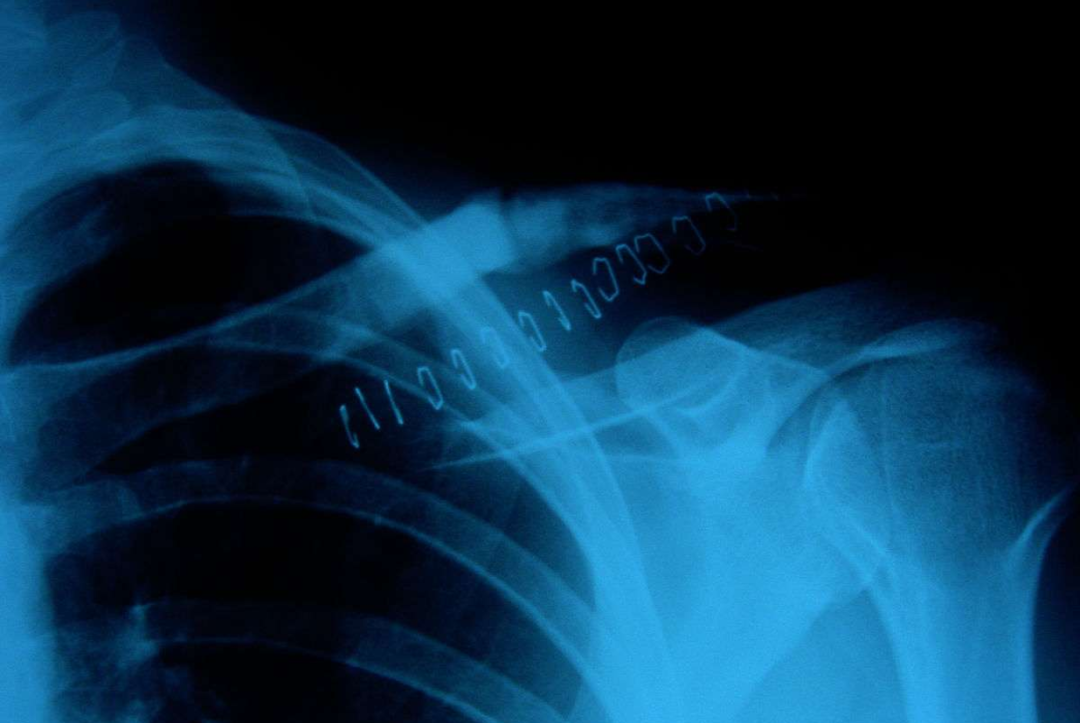

钢板和螺钉固定

A.锁骨骨折, B.前方钢板固定

双微型碎片钢板

锁骨骨折的切开复位内固定